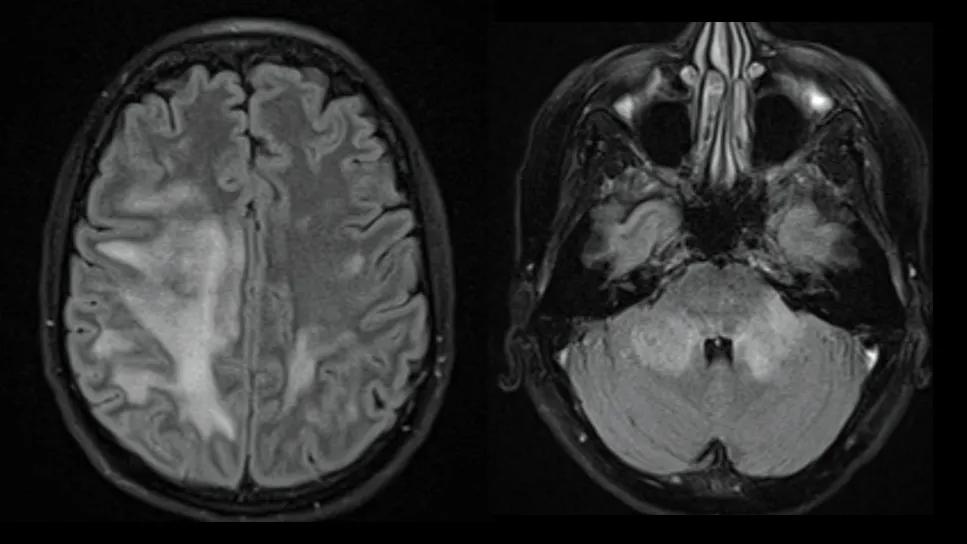

two brain MRIs side by side

Myelin oligodendrocyte glycoprotein antibody-associated disease (MOGAD) results in volume loss in all brain regions over time, with relative preservation of deep gray structures compared with multiple sclerosis (MS). Disability seen in MOGAD patients is associated with these volume losses.